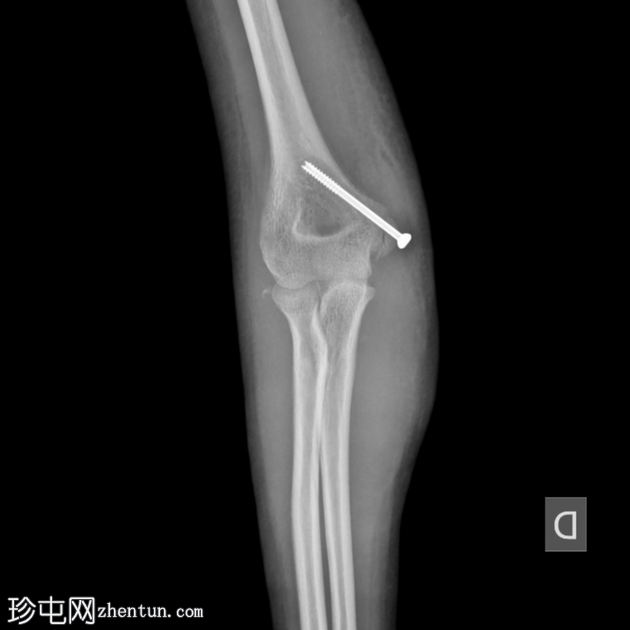

术后

X线片

5.png

正位片

侧位片

使用空心螺钉对内上髁进行有效复位。

位置良好的硬物